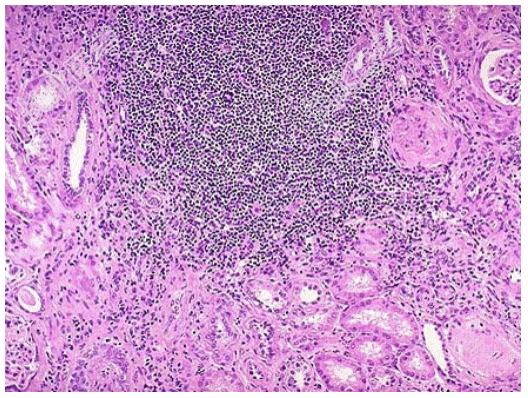

- [材料题] 患者女性,53岁,双肾缩小,表面可见不规则瘢痕,两侧改变不对称,切开,皮髓质界限不清,肾乳头萎缩,肾盏和肾盂因瘢痕收缩而变形,肾盂黏膜粗糙;巨检如图,镜下如图所示。

- 简答题1、应首先考虑的是?

- 简答题2、该疾病需与哪些疾病进行鉴别诊断?